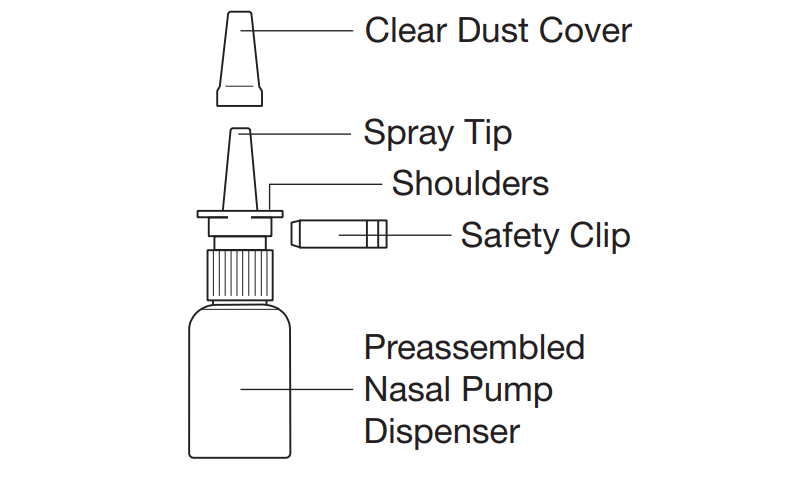

How to prepare Synarel for use

Before you use a bottle of Synarel for the first time you have to prime the spray

pump.

CAUTION: Avoid breathing in the spray during priming.

Follow these steps:

1. Remove the safety clip and the clear plastic dust cover from the spray bottle.

2. Put two fingers on the "shoulders" of the spray bottle and put your thumb on the bottom

of the bottle.

3. Hold the bottle in an upright position away from you. Apply pressure EVENLY to the

"shoulders" and push down QUICKLY AND FIRMLY until a fine spray occurs. Usually the

spray will appear after about 5 to 10 pumps.

4. The pump is now primed.